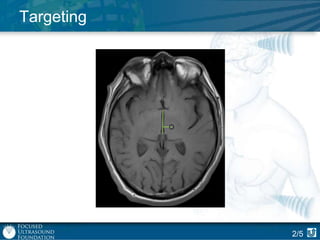

Targeting

2/5

Procedure: Targeting

Structures

to be avoided

Region to be

treated